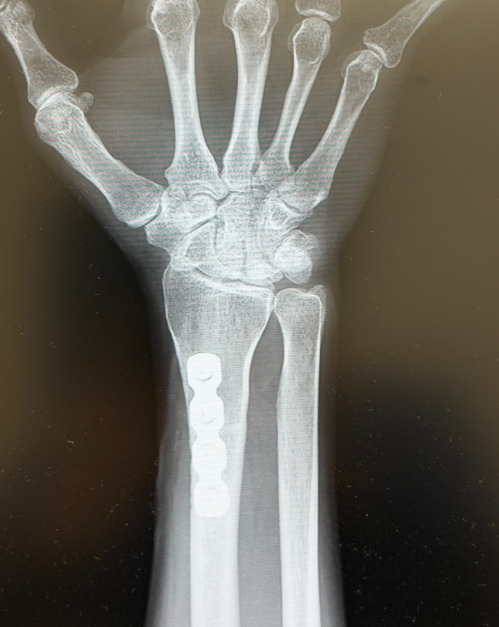

Stage II以上、あるいは保存治療に抵抗性を示す症例では手術治療を検討します。手術法は大きく分けて、月状骨血行再建術、月状骨除圧術、月状骨の摘出・置換術、そして関節症変化が進行した症例に対する救済手術(salvage手術)の4つに分類されます。具体的な術式の選択に関しては議論の余地があり、施設によって方針が異なりますが、一般的には尺骨バリアンス(橈骨と尺骨の長さの均衡)や病期に応じて決定されます。

Stage IIやStage IIIAの症例で、尺骨が橈骨より短い「ulnar minus variance」の場合、橈骨短縮骨切り術を施行します。 尺骨が橈骨と同じか長い「ulnar zeroまたはplus variance」の場合は、有頭骨短縮術などを選択します。また、Stage IIに対しては、月状骨の血行再建を目的として、背側中手骨動脈や手関節橈背側からの血管柄付き骨移植を行う場合もあります。